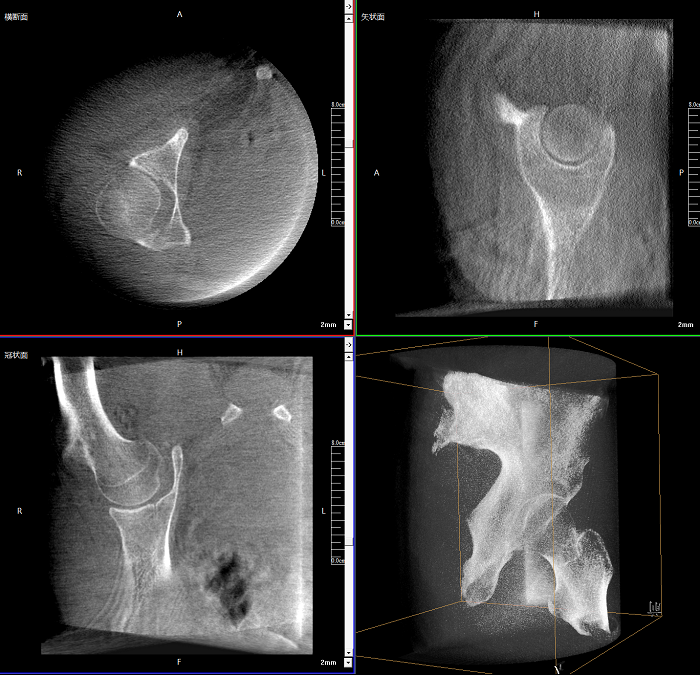

三維成像 全面觀察

任意視角、任意切面觀察

術(shù)中實(shí)時(shí)生成橫斷面、矢狀面、冠狀面及三維影像,可在任意切面、任意角度評估植入物和解剖結(jié)構(gòu)的相對位置。

Clinical picture

臨床圖片